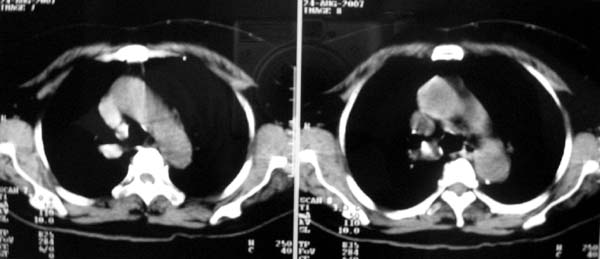

以下是引用zjzjr在2007-8-30 22:22:00的发言:[br]右上肺肺囊肿合并感染.右下肺肺大泡.左肺舌段感染.

以下是引用天南地北在2007-8-30 23:19:00的发言:[br][quote]以下是引用zjzjr在2007-8-30 22:22:00的发言:[br]右上肺肺囊肿合并感染.右下肺肺大泡.左肺舌段感染.